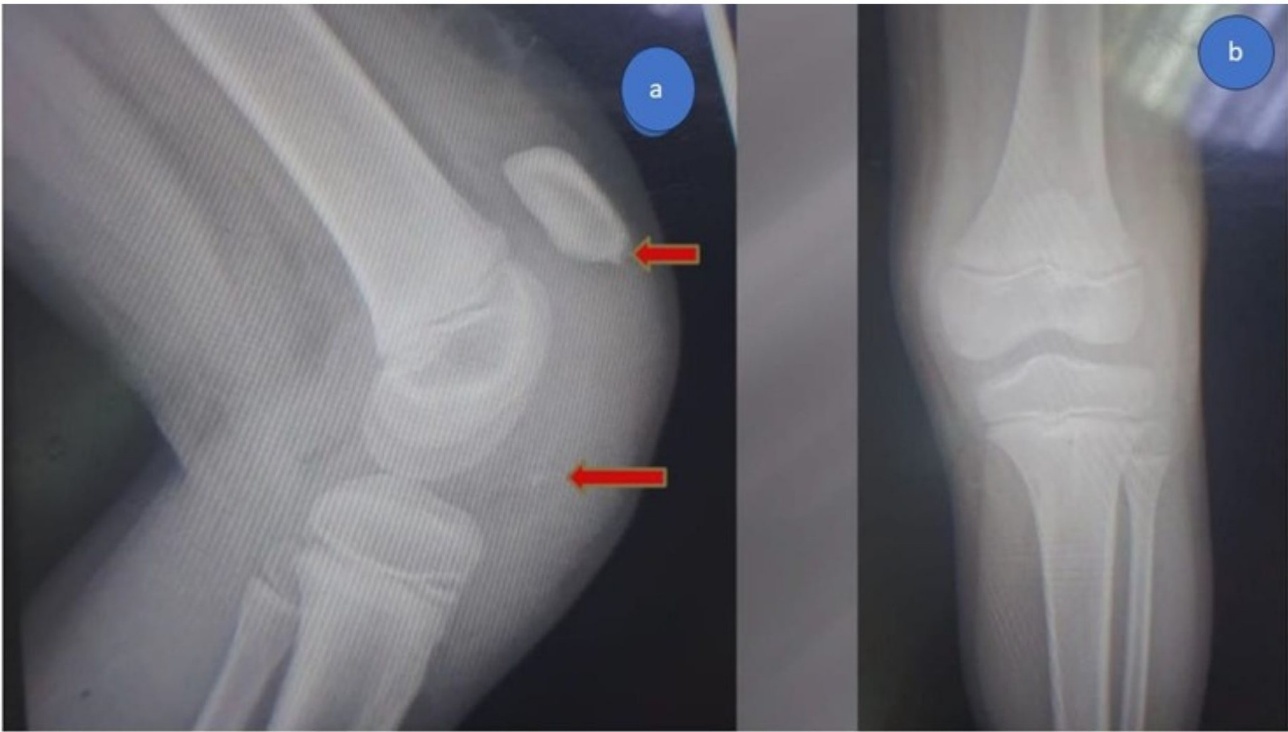

In both cases, the inferior pole of the patella demonstrated an avulsed osteochondral fragment involving approximately one-third of the articular cartilage and half of the periosteal surface. The patellar retinaculum was found to be torn and shredded, which complicated visualization, a finding commonly associated with sleeve fractures. Reduction was achieved under direct vision using reduction clamps to restore the patellar tendon–bone continuity and anatomical alignment of the osteochondral fragment.

Two parallel transosseous tunnels were created from the inferior to the superior patellar cortex using a 2.0-mm drill bit. Suture passage was facilitated with ACL wire passers to minimize fraying. Two No. 5 non-absorbable polyester sutures (Ethibond Excel®, Ethicon, USA) were woven in a Krackow fashion through the patellar tendon and osteochondral fragment. The four free suture limbs were shuttled proximally through the transosseous tunnels and tied securely over the superior pole of the patella, achieving stable fixation. The torn medial and lateral retinacula were repaired with absorbable sutures. Anatomical reduction and patellar height were confirmed both visually and fluoroscopically, using the contralateral knee as a reference. The wounds were closed in layers, and a long leg cylinder cast made of fiberglass was applied in full extension to protect the repair. (Figure 4-6)

Postoperative radiographs demonstrated satisfactory reduction and fixation (Figures 7,8).